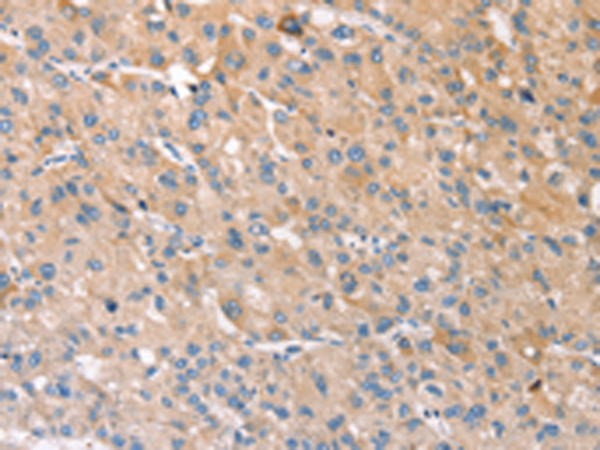

分类: 科研抗体货号: P08827别名: CARB应用: WB,IHC反应种属: Human, Mouse, Rat